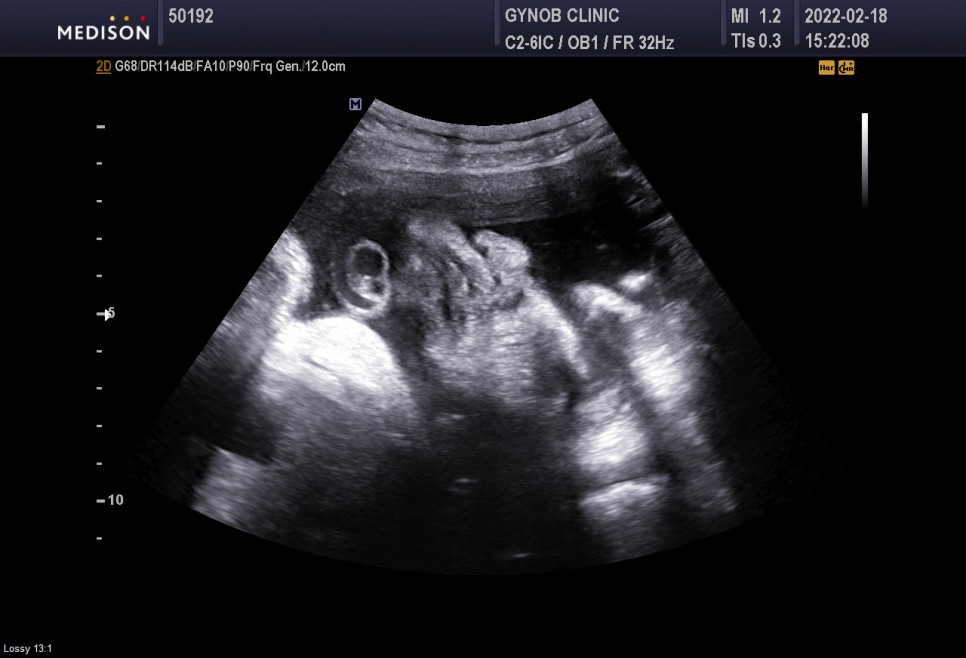

▲초음파실에서 초음파도 봤다=심상덕 원장님은 초음파를 5분 동안 꼬박꼬박 챙겨보신다.

아기의 머리 위치는 정상*경부 제대륜 1회 신경 쓸 필요는 없습니다.

- 경부 탯줄은 탯줄이 아기의 목 부분을 감고 있다는 것을 의미한다

쭉쭉 체중은 2.86kg 조금 더 큰 편.

경부제 대륜 1번 탯줄에 목을 1번 감고 있다는 뜻이다.너무 신경 안 써도 될 것 같아

느긋한 얼굴 ㅋㅋㅋ 귀여워 ❤️